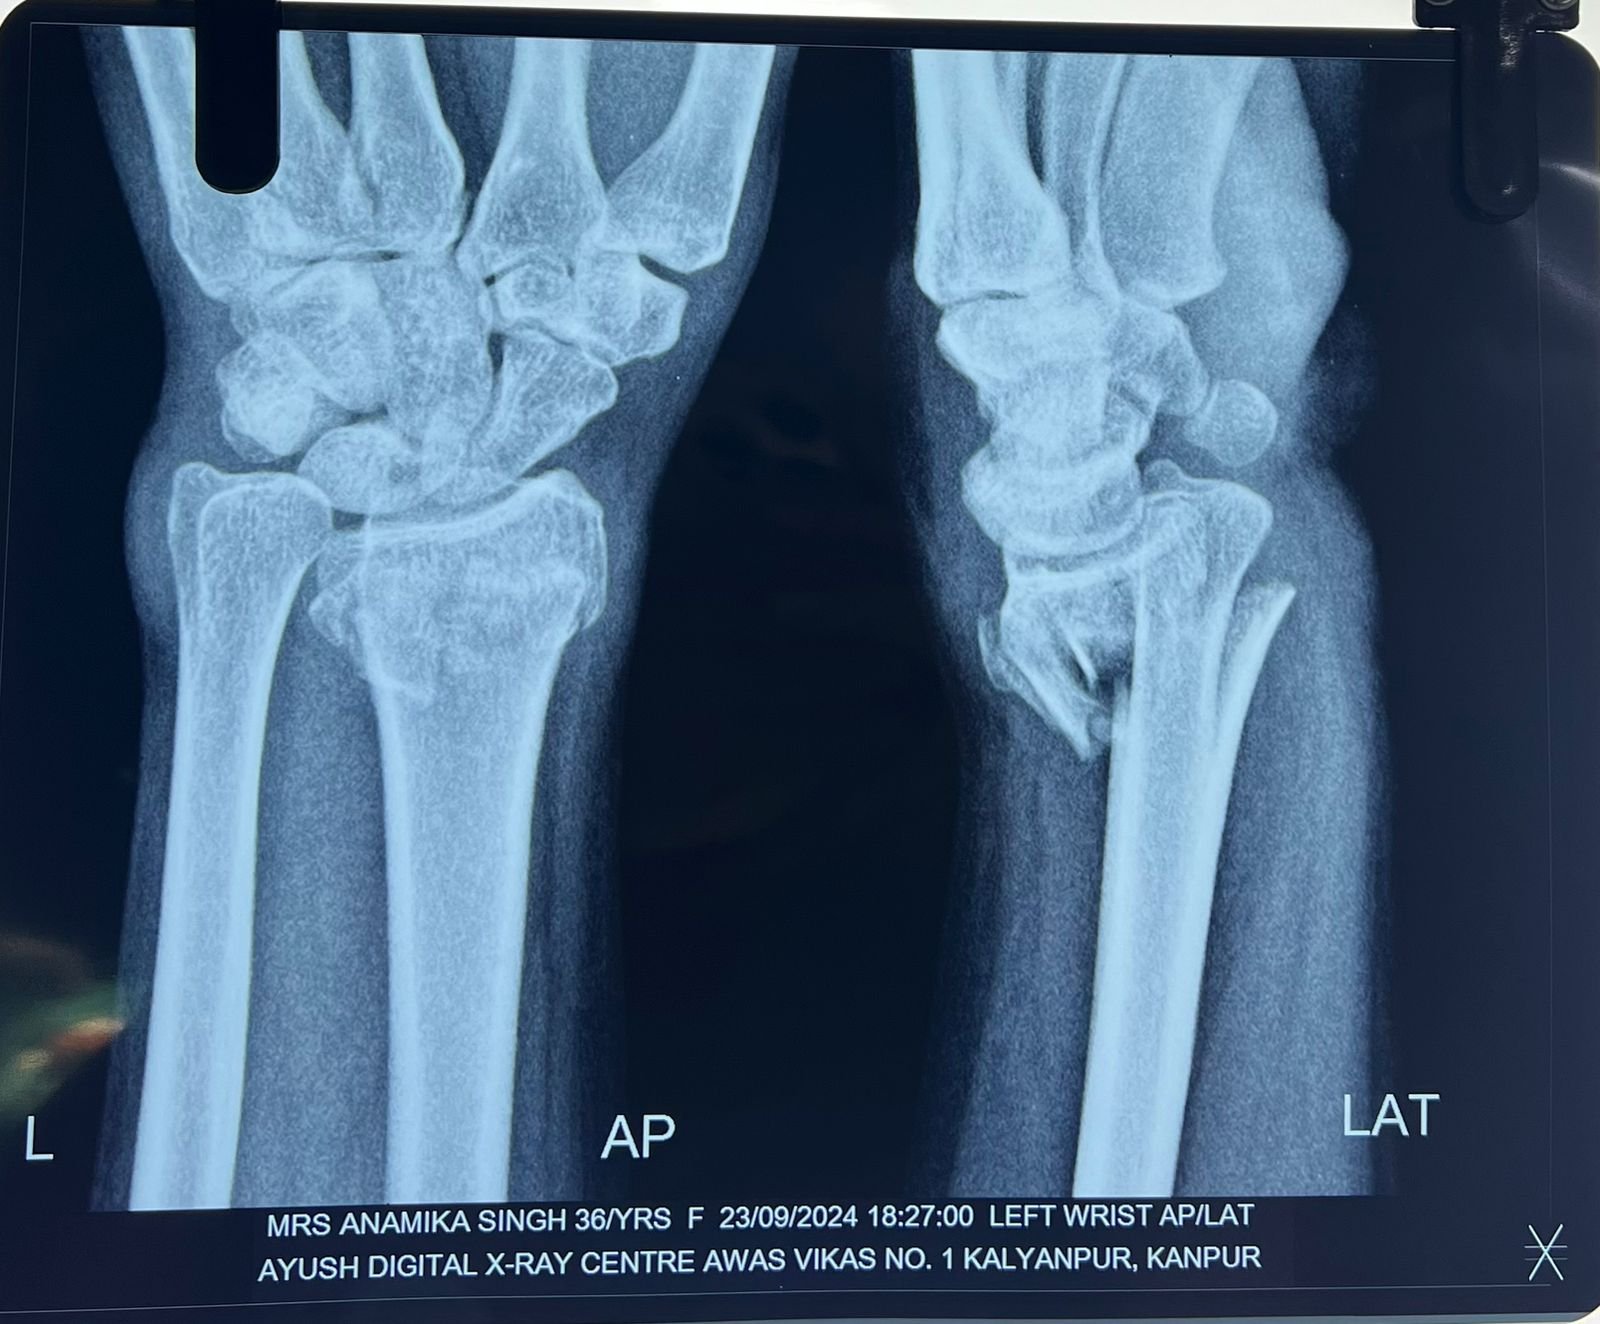

& fibula | Heal fracture pre & postop | Clavicle

fracture pre &